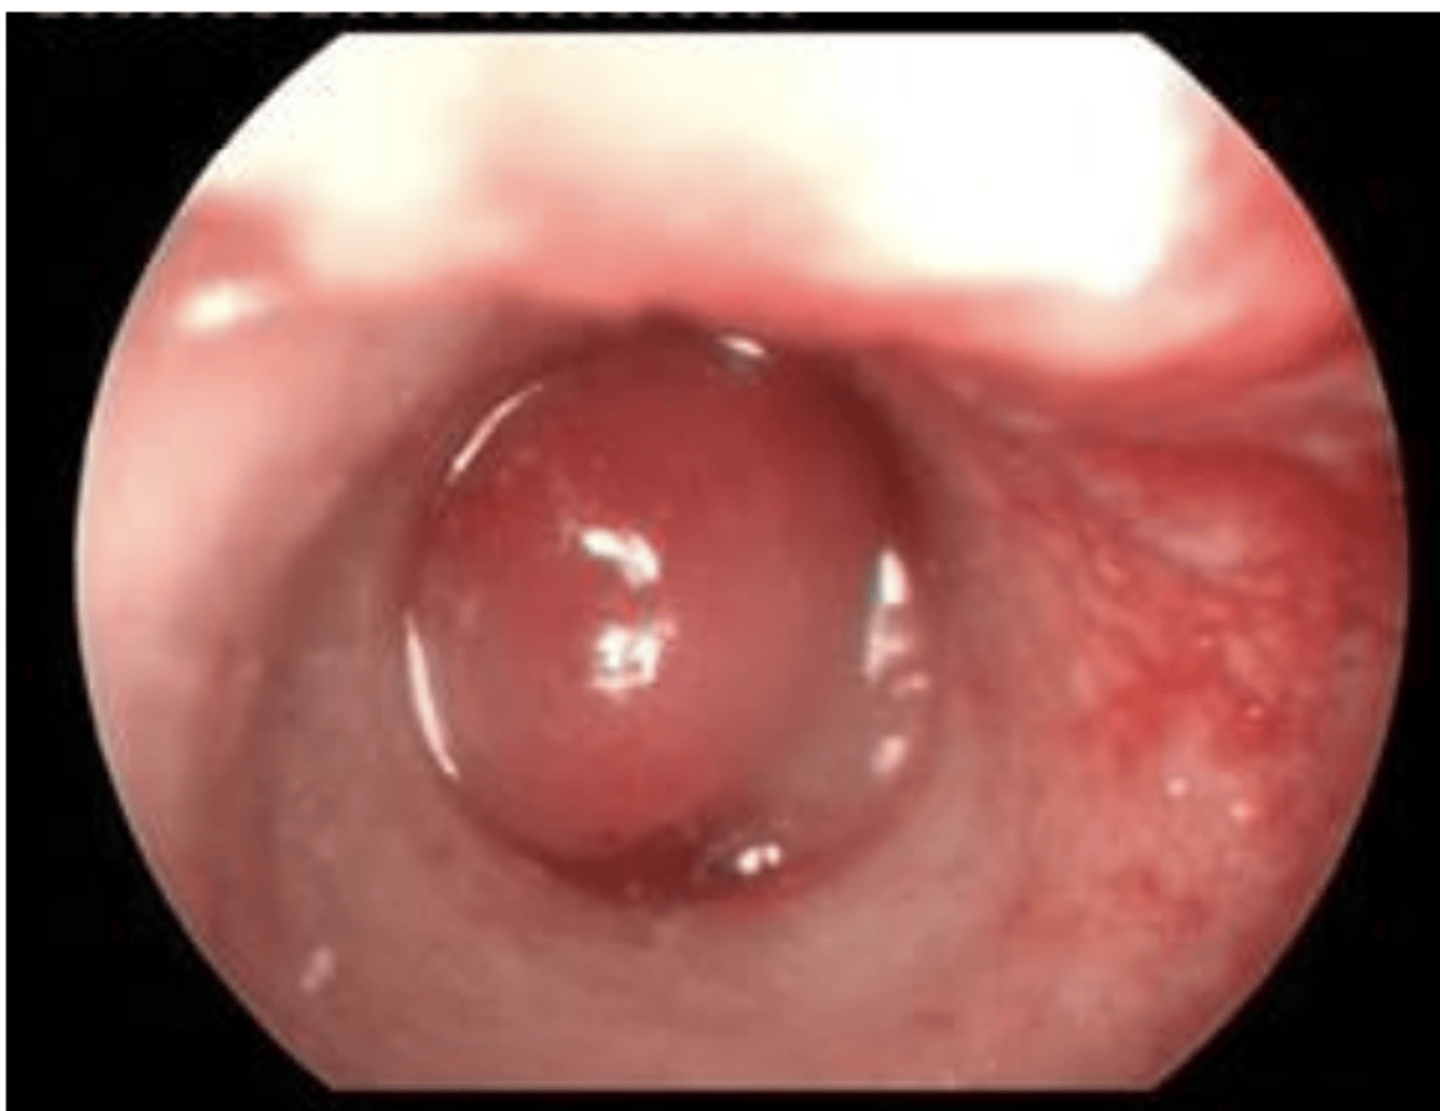

What are the differential diagnoses for this cat?

polyp, mass, or growth (most likely polyp)